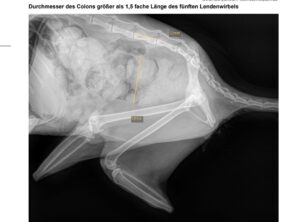

Unser lieber älterer Fundkater aus Oebisfelde begann vor einigen Tagen immer im Kreis zu laufen. Die ersten Untersuchungen in der...